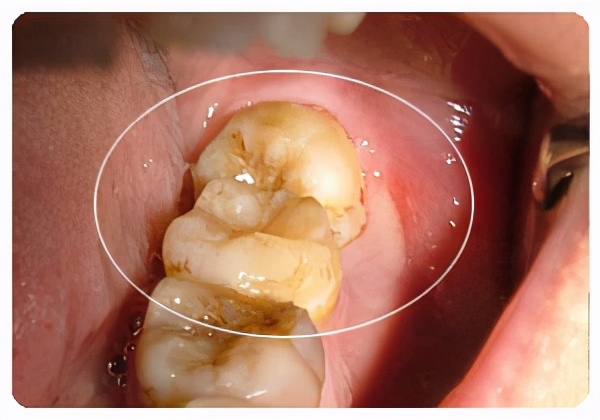

再者,就算智齿位置是正的,但处于最末端的牙齿,清洁起来很麻烦,很容易嵌塞食物,引起口腔炎症等问题。

(智齿引起食物嵌塞)